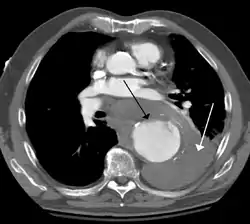

Contrast enhanced CT of a ruptured large (7 cm) thoracic aneurysm, with black arrow indicating the aorta, and white arrow blood in the thorax- Ruptured thoracic aortic aneurysm as seen on ultrasound[13]